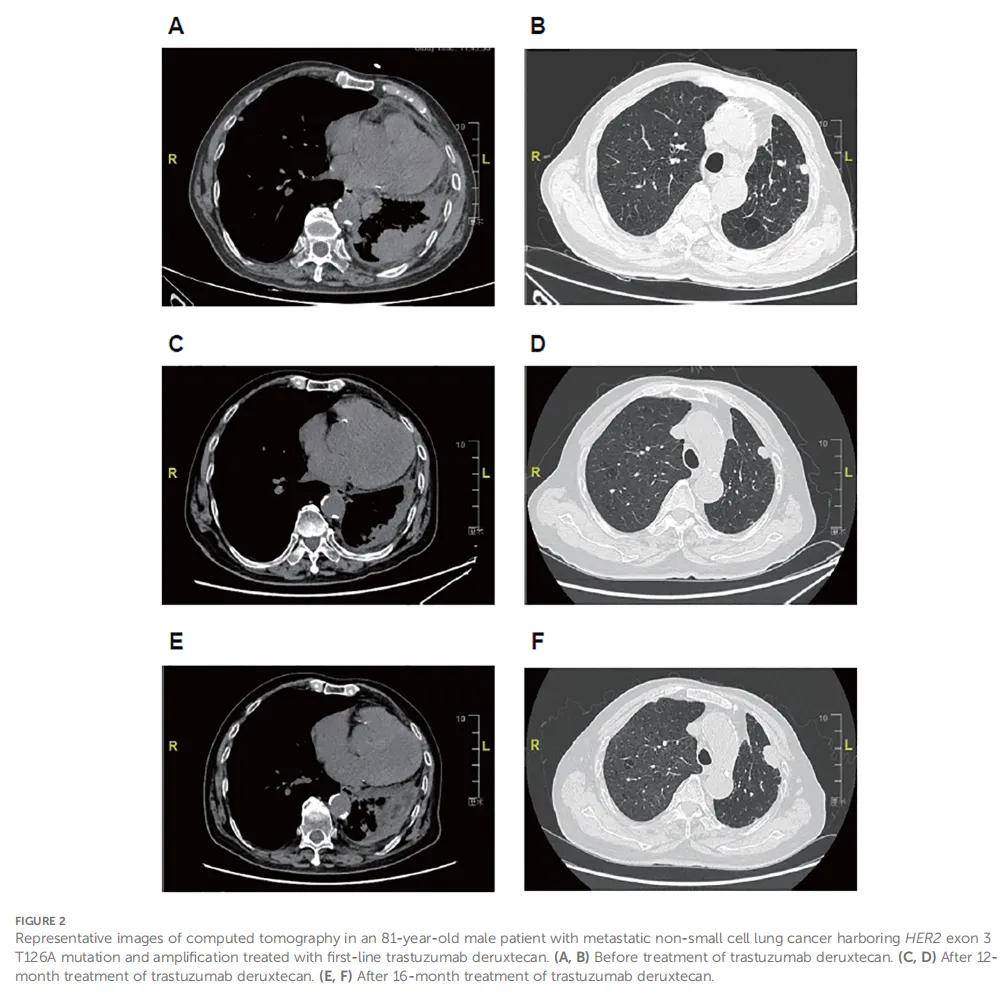

患者男,81 岁,因转移性非小细胞肺癌(NSCLC)治疗于 2023 年 3 月入院。该患者于 2020 年 6 月被诊断为左下叶低分化肺腺癌,并接受了胸腔镜辅助根治性切除术。病理分期为T2aN1M0。术后,患者于 2020 年 7 月至 2020 年 8 月接受培美曲塞(700 mg,第 1 天)联合奈达铂(100 mg,第 2 天)辅助化疗,共 2 个 21 天周期,后因无法耐受毒性而停药。2023 年 2 月,CT显示双肺转移性肿瘤病灶。患者有冠心病、重度高血压病史,吸烟史70年。本次入院时,体格检查及实验室检查显示完全性右束支传导阻滞,血红蛋白 78 g/L,东部肿瘤协作组(ECOG)体力状况评分为 3 分,无其他显著异常。CT显示双肺多发结节(最大者边界不清:49×28 mm),残余左肺炎症伴癌性淋巴管炎,多发淋巴结转移(锁骨上窝、膈脚、左心膈角、右肺门及纵隔;最大短径:23 mm),左侧胸膜增厚(图2A、B)。疾病分期为rpT4N3M1a。采用手术切除标本进行基因检测,结果显示HER2突变(3外显子T126A)及HER2扩增。患者自 2023 年 3 月起接受德曲妥珠单抗(T-DXd)(3.4 mg/kg,每3周一次)治疗,最佳疗效为部分缓解(PR)(图2C、D),ECOG体力状况评分改善(从 3 分降至 1 分)。德曲妥珠单抗单药治疗18个周期期间,出现恶心、乏力,均为 2 级。2024 年 7 月,彩色超声显示左锁骨上淋巴结转移,CT显示疾病进展(图2E、F)。随后在德曲妥珠单抗治疗基础上加用安罗替尼(10 mg,每日一次)。1 个 21 天周期治疗后,因耐受性差,德曲妥珠单抗换为培美曲塞(700 mg,第 1 天),同时继续安罗替尼治疗。

▲图2 患者代表性CT影像